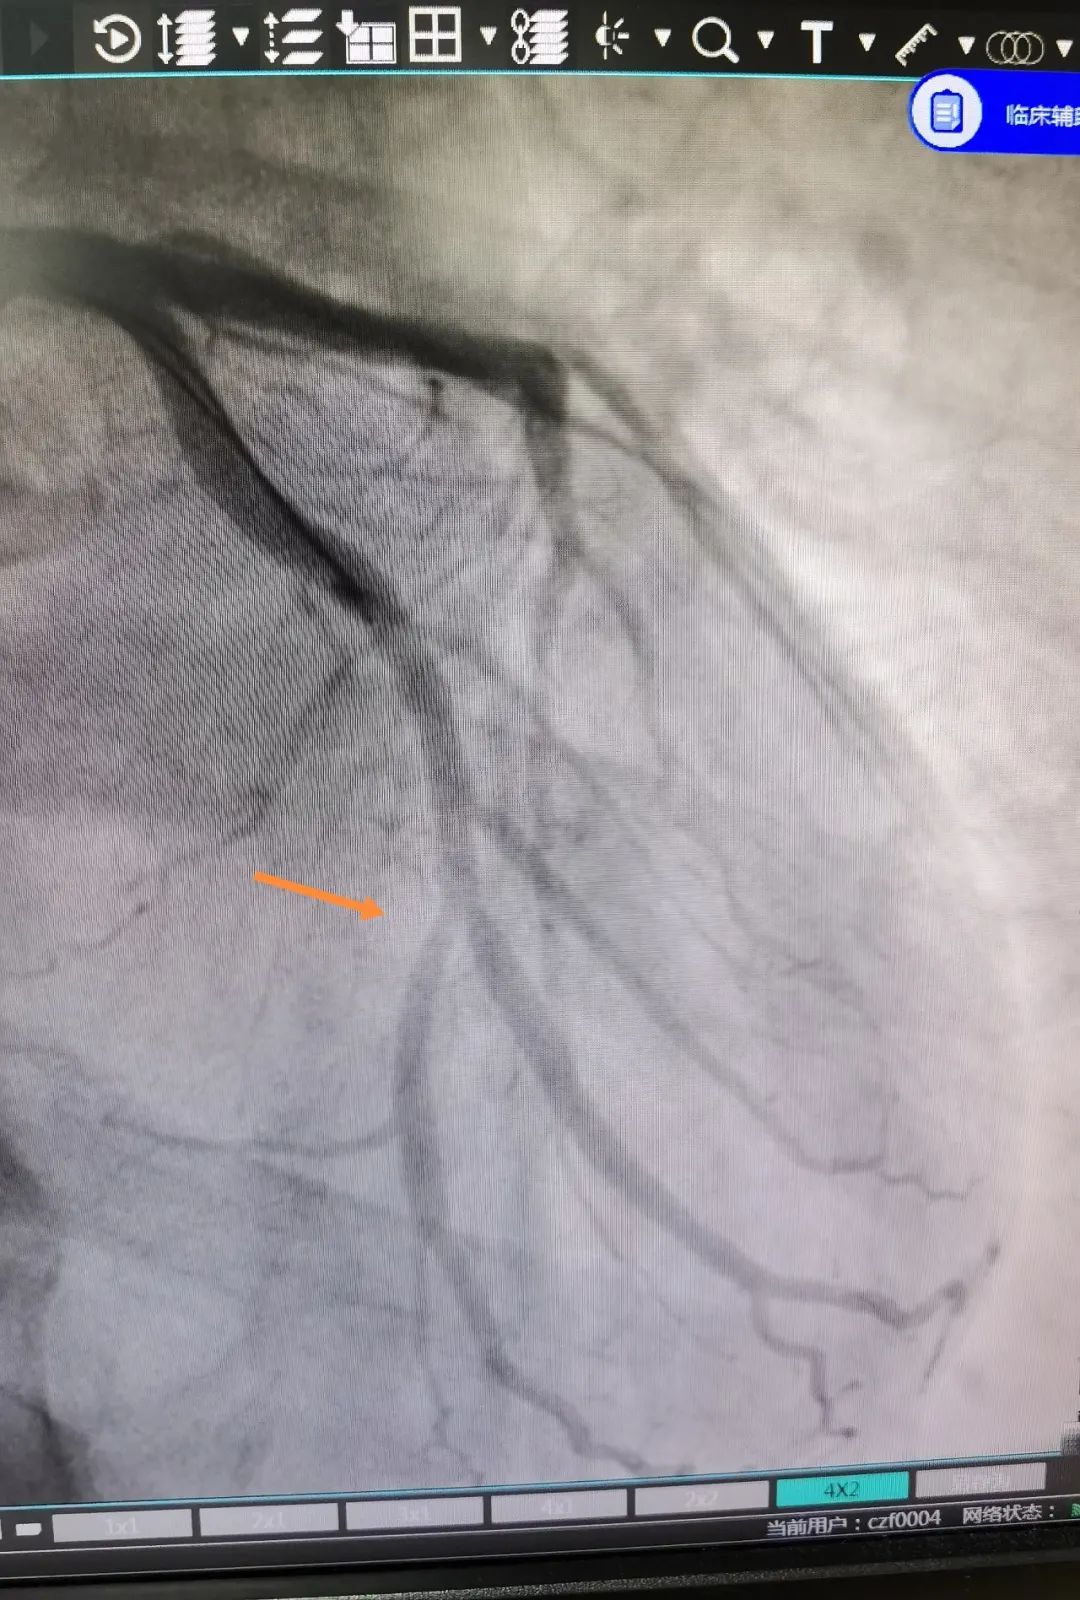

这位患者在 QFR 指导下对于分叉病变使用药物球囊治疗,避免了支架的植入对分叉另外一根血管的压迫,从术前和术后的 QFR 数值来看,手术收到了非常好的疗效。同时该患者不需要长期服用双联抗血小板药物,只需服用双联抗血小板药物一到三个月,因此对于特定病变和特定人群具有不少优势。

术后影像

术后影像学效果和血流恢复情况都非常满意,此项手术的成功开展也是继 8 月 21 日成功实施经皮主动脉瓣置换(TAVI)后的又一例嘉湖地区首例。